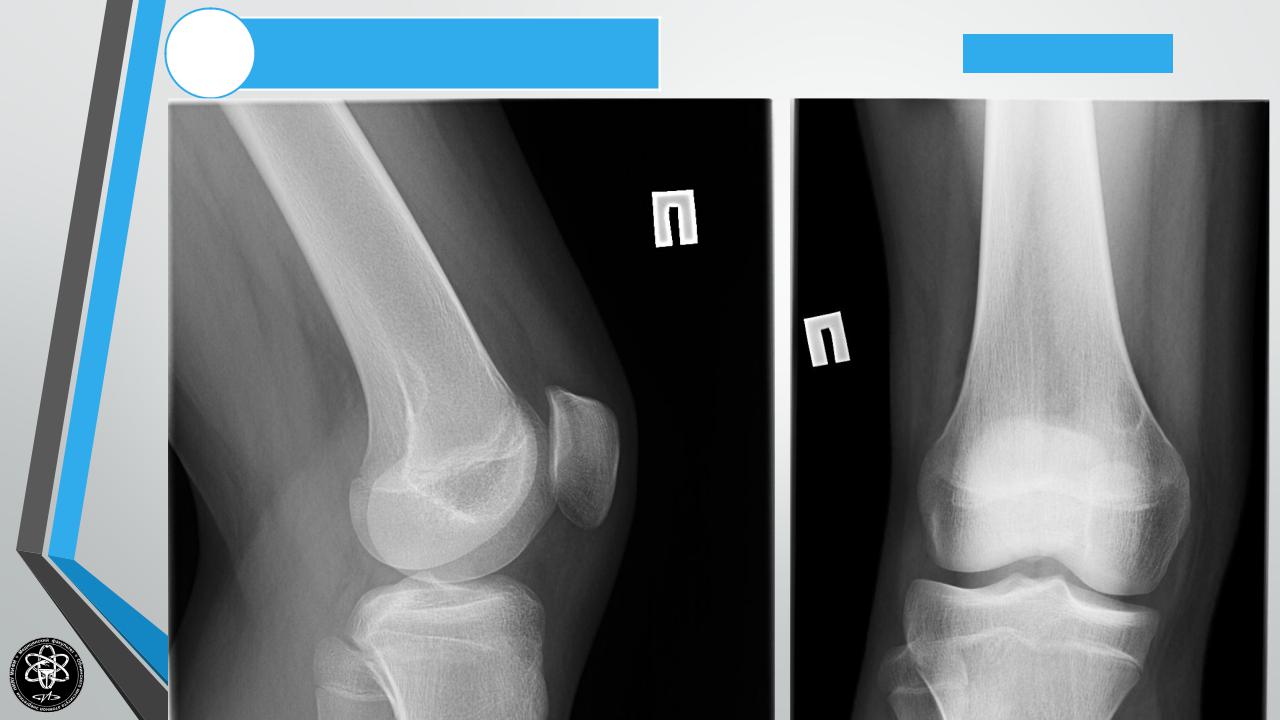

Остеоид-остеома